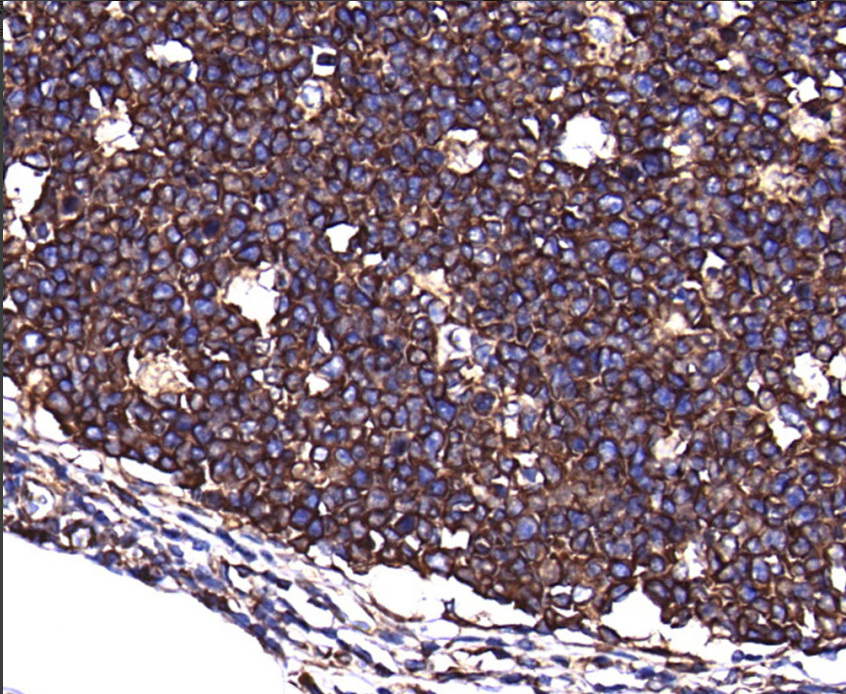

Clone number: 37B

isotype: mouse monoclonal antibody

Cellular localization: cytoplasm

Tissue: paraffin/frozen

Positive controls: skin/kidney/stomach/rectum

Tubulin-β is a neuron-specific marker that is expressed in breast cancer and some malignant epithelial tumors. Studies have shown that Tubulin-β expression is also present in malignant non-neurological tumors with high tissue grade, and it has also been shown that Tubulin-β is a marker of cancer cell resistance to paclitaxel analogs.

Tubulin-β antibody reagents can specifically bind to Tubulin-β molecular antigens. Immunohistochemistry kits containing Tubulin-β antibody reagents are suitable for the auxiliary diagnosis of breast cancer and small cell lung cancer.